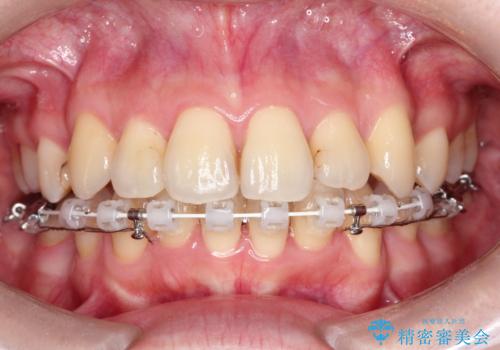

ガタガタの抜歯矯正を裏側ワイヤーを使っての目立たない矯正

- ハーフリンガル

- 八重歯とガタガタを主訴に来院されました。

目立たないワイヤー矯正を希望されたので、上下左右のはを1本ずつ抜歯して、ハーフリンガル(上顎だけ裏側)にて矯正をすることにしました。